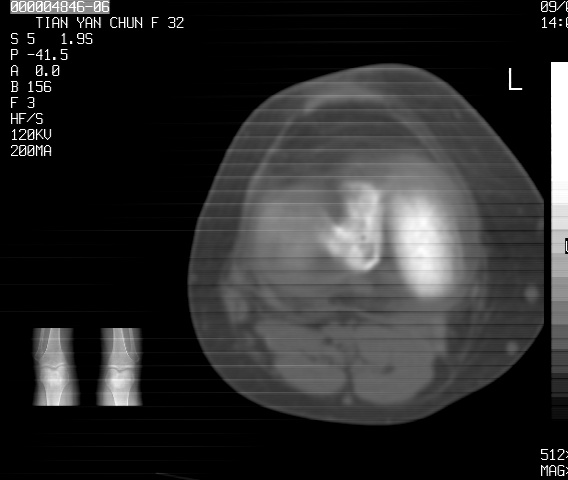

标题: CT18487:请会诊,女32岁,左膝疼痛数日 [打印本页]

标题: CT18487:请会诊,女32岁,左膝疼痛数日

关节面软骨有硬化环考虑退行性变

定位片可见髁间棘骨质增生,支持膝关节退行性变。

定位片可见髁间棘骨质增生,支持膝关节退行性变。建议mri 检查

考虑骨性关节炎